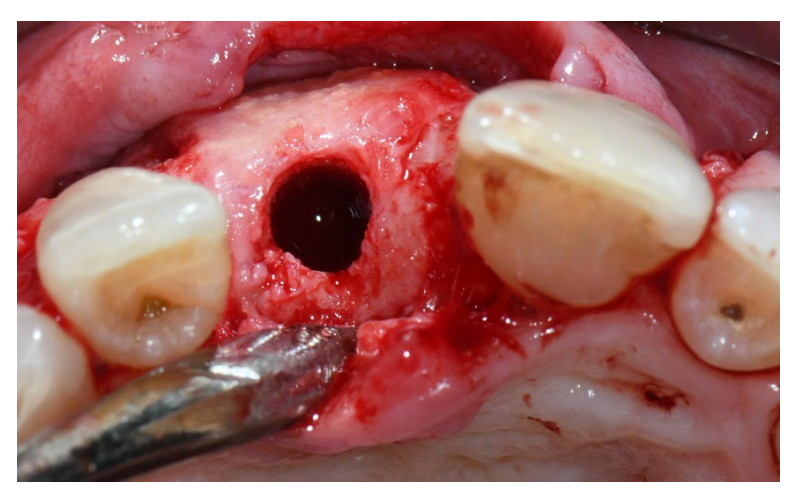

In group B, GBR (control group, Figures 5–8), just a fibrine sponge was inserted into the socket to stabilize the blood clot.

In group B, eight weeks after tooth extraction, an intrasulcular incision was made using a no. 15C Bard-Parker blade, and a full-thickness flap was elevated beyond the mucogingival junction and at least 5 mm beyond the bone defect. Two vertical incisions were placed at least one tooth away from the area to be augmented. Multiple decortication holes at the recipient site were performed with a round bur. The residual alveolar socket was grafted with particles of porcine-derived cancellous anorganic bone material (Zcore, DeOre). Then, a collagen membrane (Cytoplast RTM Collagen, DeOre) was shaped according to the regenerated bone defect and was fixed with three to five titanium pins (Supertack, MCbio s.r.l., Lomazzo, Italy), on the buccal and lingual/palatal sides. The membrane was trimmed to the entire graft volume, one to two millimeters before the adjacent teeth surface. A periosteal incision was performed between the two vertical incisions to allow a completely tension-free closure of the flap. The flaps were then sutured in two layers in order to prevent exposure to the membrane (Cytoplast PTFE Suture 4-0). Horizontal mattress sutures were first placed 4 mm from the incision line; then, single interrupted sutures were placed to close the edges of the flap. Vertical incisions were sutured with single interrupted sutures. The single interrupted sutures were removed between 10 and 14 days post-surgery, and mattress sutures were removed two to three weeks after surgery. One g of amoxicillin (or 300 mg of clindamycin) was administered every 12 h for eight days after tooth extraction and bone reconstruction. Paracetamol 500 mg plus codeine 30 mg were prescribed as needed. Patients were instructed not to take them in the absence of pain.